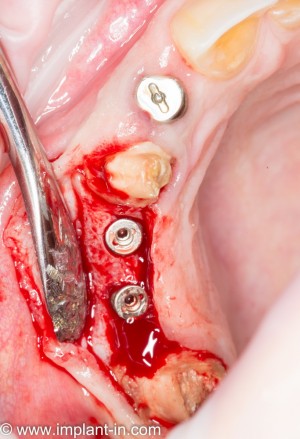

в ходе второго этапа было установлено три импланта в боковом сегменте верхней челюсти, удален ретинированный зуб мудрости, проведен синуслифтинг

Вторая операция заняла чуть больше времени (90 минут), поскольку потребовалось удаление ретинированного зуба мудрости и синуслифтинг. Послеоперационные явления более выраженные — отек держался в течение нескольких дней, болезненных ощущений почти не было.